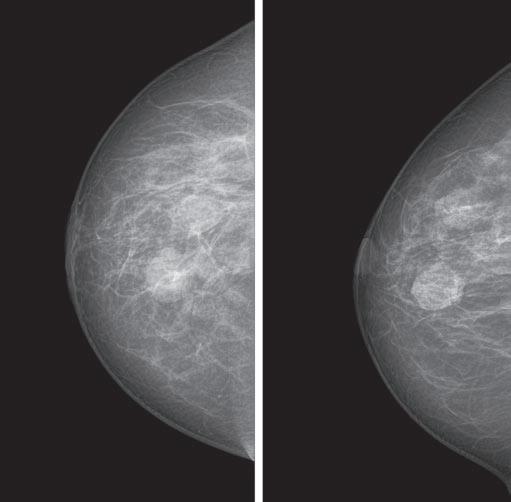

Cover Story Breast tests that Could Save Your Life

A yearly mammogram is the gold standard for breast cancer screening and detection. Mammography is the only test that has been scientifically proven to save lives. Still, it’s not infallible.

“In women with very dense breasts, mammography will miss cancer 58% of the time,” says Thomas Kolb, M.D., a breast cancer radiologist.

Dense breasts contain more glands, ducts, and connective tissue than fat. Breasts tend to be denser during a woman’s reproductive years. Density makes it harder to detect suspicious lumps on a mammogram; that’s because glandular tissue appears white on a mammogram, just like a mass can.

tomosynthesis, or 3D mammogram, takes images of breast tissue from multiple angles.

Also, women with dense breasts who undergo tomosynthesis are 40% less likely to be called back for additional imaging.

Should you ask for it? Screening tomosynthesis is in order if you have dense breasts or you’re at average or intermediate risk for breast cancer.

Fortunately, there are new tools that can give a more precise diagnosis, especially if you have dense breasts or you’re at higher risk for breast cancer because of your personal or family health history.

Here are three that may give you a clearer picture of your breast health — and could possibly save your life.

Tomosynthesis

The latest in breast cancer detection technology, tomosynthesis, also known as 3D mammogram, is a digital mammogram that takes images of the breast in thin slices from multiple angles.

Tomosynthesis takes an arc of pictures through each breast, in 5-millimeter slices, which are then reconstructed into a three-dimensional image.

It allows radiologists to see through the breast tissue so they can more easily distinguish a true

mass from overlapping structures that can hide or mimic cancer, such as ligaments or glandular tissue.

Tomosynthesis can be used for screening and diagnostic mammograms.

Pros/cons: Compared to a digital (2D) mammogram, tomosynthesis is more precise. Studies show that three more women per thousand will receive a cancer diagnosis with tomosynthesis, compared to a digital mammogram.